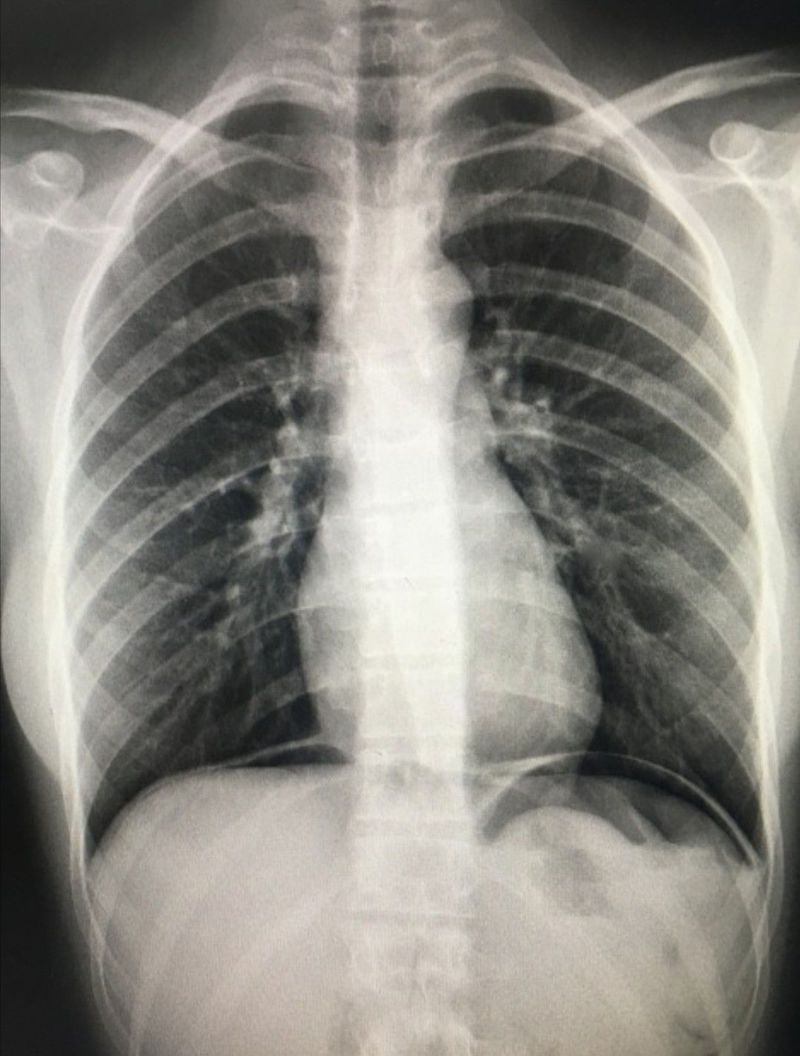

Pericardial effusion.. Sign - Money bag/water bottle /leather bottle